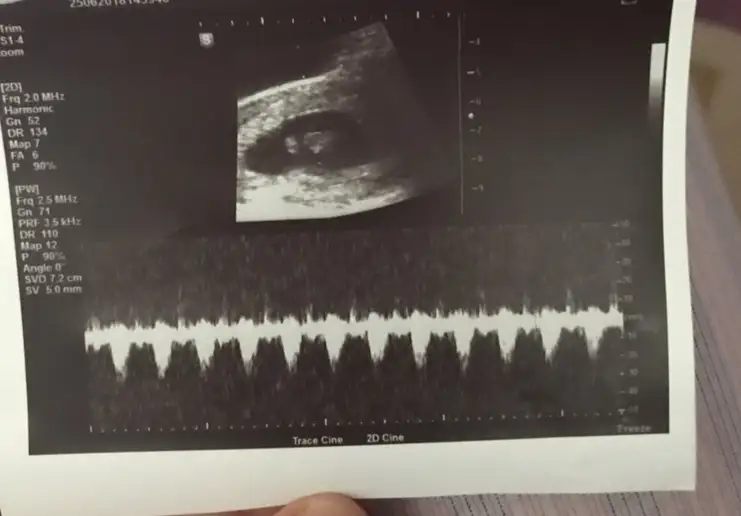

Gözün aydin cnm ♥Kızlar kalp atışını duyduk çok şükür 6+4 Ama kalp atışı bana yavaş geldi 110 doktor normal dedi sizce nasıl 110

ohh cok sevindim arkadaşım. stresinde azalmıştır boylelikle. bizim bebenin kalbi de yanılmıyorsam 120 atmıştı. zamanla rtıyor demişti amaKızlar kalp atışını duyduk çok şükür 6+4 Ama kalp atışı bana yavaş geldi 110 doktor normal dedi sizce nasıl 110

Sagol canm benim.Nabzim 100 e fırladı heyecandan o an şükür duyduk inşallah artarohh cok sevindim arkadaşım. stresinde azalmıştır boylelikle. bizim bebenin kalbi de yanılmıyorsam 120 atmıştı. zamanla rtıyor demişti ama

Kalp atışı normal canim 140dan aşağı atarsa erkekmis oyle duymuştum hayırlısi olsun

doktoruna sorman ve onunda soylemesi gerekiyordu diye biliyorum ben.Kızlar kalbinin kaç attığı nerede yazıyor